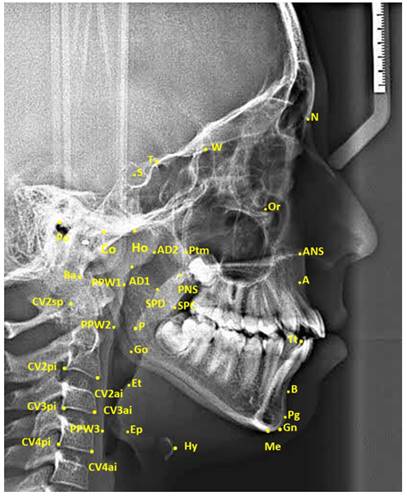

Lateral cephalometric films included in the study were calibrated on the Planmeca Romexis (Planmeca Romexis Viewer®, Helsinki, Finland) software program and were printed on tracing paper in 1:1 dimension in real size. Then, measurements were made by drawing the following cephalometric points and planes with the help of a 0.3 mm lead pencil. The cephalometric landmarks used in the study are shown in Figure 1, pharyngeal airway measurements in Figure 2, and hyoid measurements in Figure 3.

Figure 1

| Figure 1 The Cephalometric Landmarks |